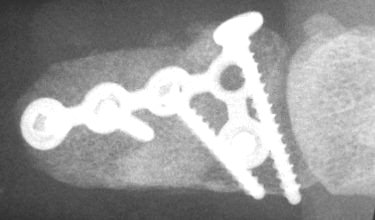

Late Xrays.